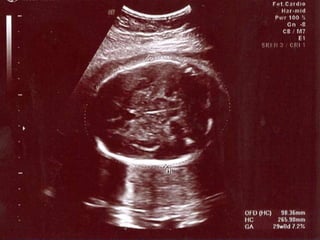

AC

 Ölçüm zor

 KC transvers diameterin en büyük olduğu

yerden ölçülür

 Sol ve sağ hepatik ven birleşir

 Elips cilte uygulanır